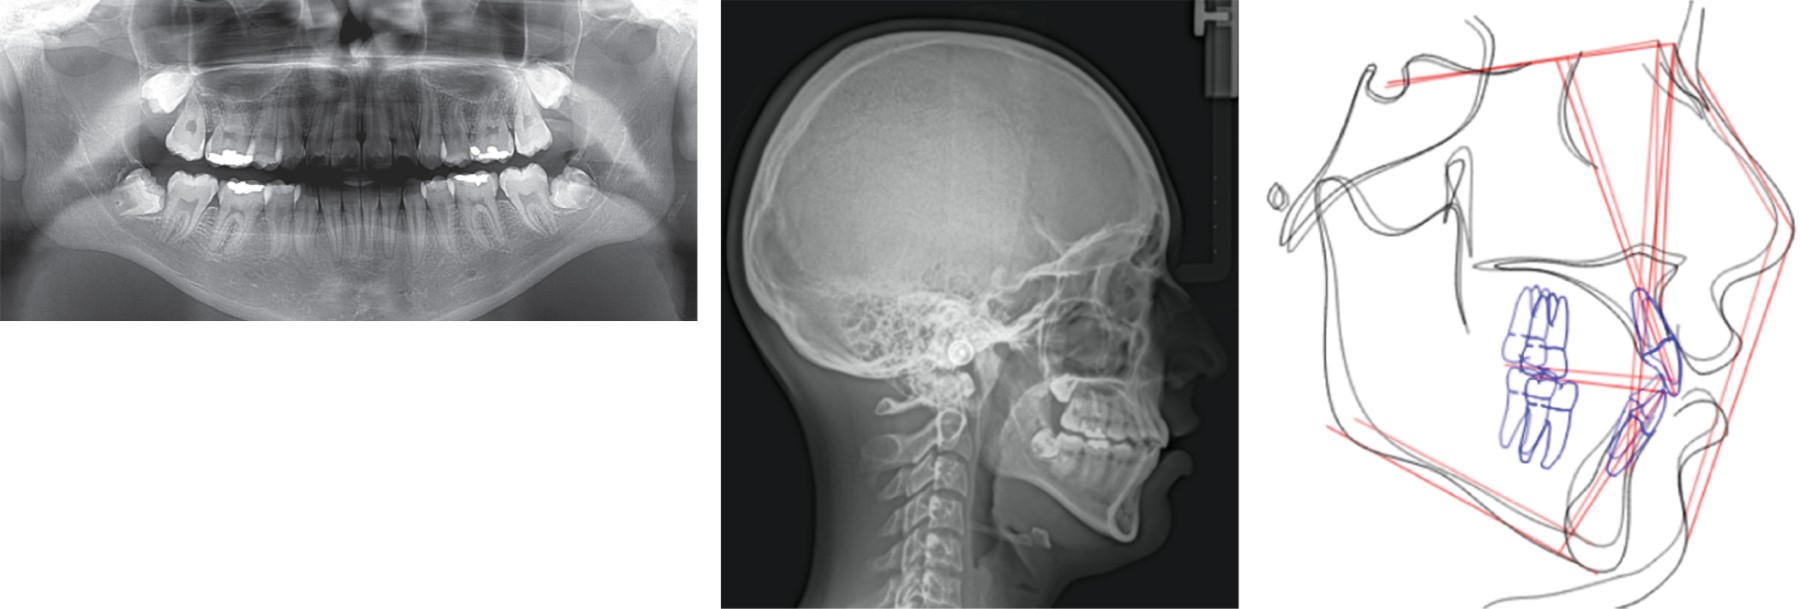

Detallado y finalización: una vez cerrados los espacios, se pidió radiografía panorámica para valorar paralelismo radicular y se realizaron las recolocaciones de brackets en los órganos dentarios 15, 12, 22, 25, 45 y se retiró el arco transpalatino (Figura 5). Se colocaron tubos en segundos molares inferiores, se usaron elásticos de asentamiento posterior ¼" 4.5 onzas y se retiró el arco lingual (Figura 6). Una vez que se lograron los objetivos, se retiraron los brackets (Figura 7).

Se eliminó la mordida cruzada posterior unilateral derecha, se establecieron caninos en clase I; se mantuvo la clase I molar; se obtuvo adecuada sobremordida horizontal y vertical, corrección de la curva de Spee y formas de arco adecuadas; se eliminó el apiñamiento. Se logró un adecuado asentamiento de la oclusión con guía anterior y se mejoró el perfil disminuyendo la convexidad facial. Además, periodontalmente el margen gingival de los caninos se muestra en buena posición (Tabla 1) (Figuras 7 y 8).

Figura 6

Figura 7

Figura 8